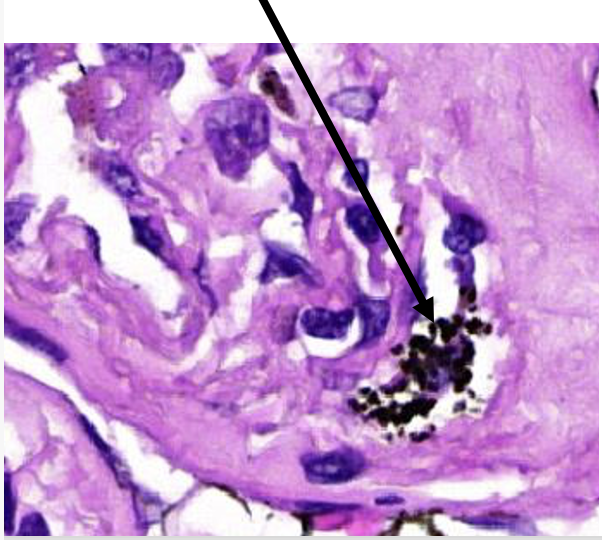

Kenmerken kapsel van silicone borstimplaat

fibrose (bindweefsel rond silicone)

vreemd lichaam materiaal (silicone)

macrofagen, meerkernige reuscellen, lymfocyten

vorming pseudokapsel door macrofagen met bindweefsel

wat wordt er aangeduid

meerkernige reuscellen